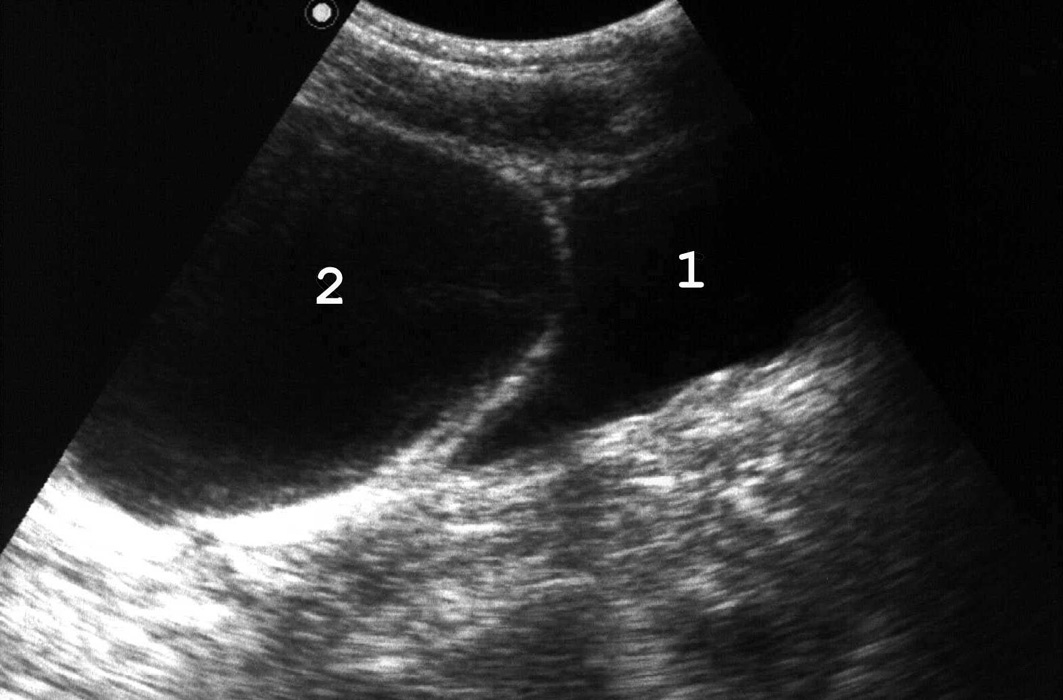

Рис. 4. Сонограмма мочевого пузыря в норме: 1 − мочевой пузырь; 2 − простата; 3 − стенка мочевого пузыря нормальной структуры и толщины. (Продольное сканирование, конвексный датчик 5 МГц, “Logiq-500”).

Рис. 5. При хронической задержке мочи вначале развивается гипертрофия мышечной оболочки мочевого пузыря: 1 − мочевой пузырь; 2 − увеличенная простата; 3 − утолщенная стенка мочевого пузыря. (Продольное сканирование, конвексный датчик 5 МГц, “Logiq-500”).